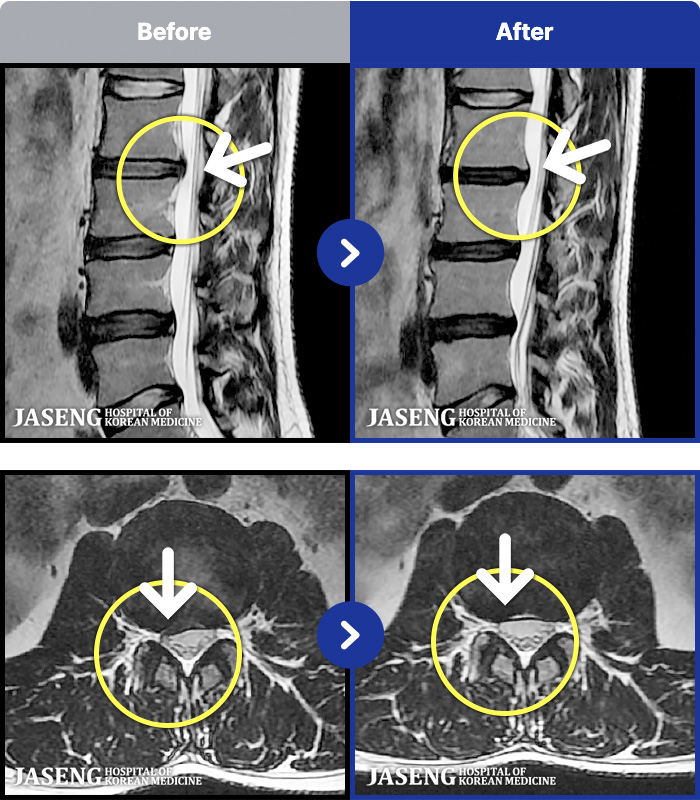

[뱸] 19.11.28~25.05.06